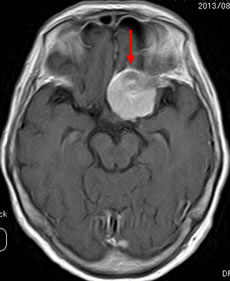

当院での症例をお示しします。症例は66才女性、進行する左眼の視力(左:手動弁)、視野障害にて当院来院。MRIにて赤矢印のように左蝶形骨内側に大きな腫瘍を認めます。開頭手術治療前に腫瘍の栄養血管にカテーテルを入れて、固体塞栓物質を造影剤と混ぜて注入します。最後に再開通しない様プラチナコイルを留置して終了します。その2日後に腫瘍摘出を行いましたが、出血は少量で輸血も行っておりません。視力も左は1.5まで改善し、患者さんは元気で退院しました。(図1-a・b、図2-a・b、図3-a・b、図4-a・b)

図1-a:術前 |